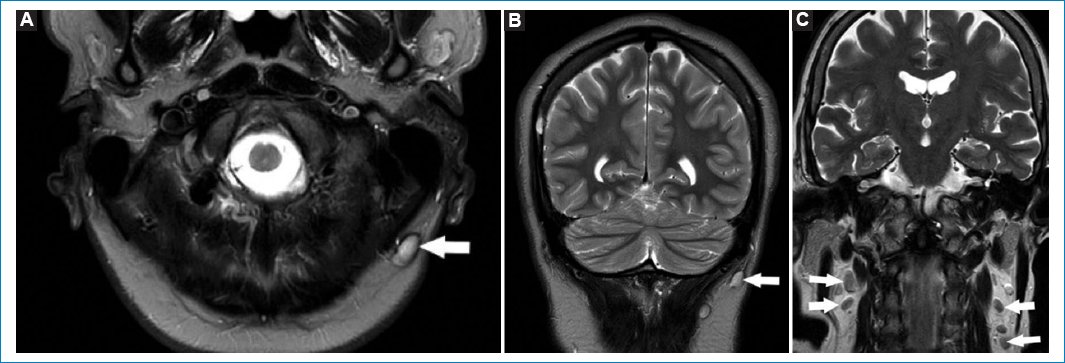

La presencia de adenopatías en cuello debe ser informada. Recordemos que las adenopatías mayores de 1 cm, en el eje corto, cambios en la señal en el tejido graso vecino, necrosis, calcificaciones o cambios en el hilio graso deben considerarse sospechosas de malignidad (Fig. 11)1,31.

Figura 11. Adenopatías en cuello. Secuencias ponderadas en T1. Cortes: axial (A) y coronales (B y C). Las flechas señalan distintos pacientes en los que fue informada la presencia de adenopatías, en contexto de un linfoma en una paciente de 27 años.

Es muy común el hallazgo de lipomas en el tejido celular subcutáneo. Se caracterizan por su naturaleza benigna y lento crecimiento. Dado su contenido adiposo son hiperintensos en T1 y T2 e hipointensos en STIR (Fig. 12)32.

Figura 12. Lipomas en cuello. Cortes axiales T1 (A) y T2 (B), y corte sagital T1 con gadolinio (C). Las flechas indican la presencia de imágenes redondeadas, bien delimitadas, hiperintensas en T1 y T2. Corresponden a lipomas en la región occipital.

La RM es el método de elección para valorar adenopatías en el espesor del tejido glandular parotídeo. La visualización de ganglios (menores de 1 cm), ante la ausencia de lesiones focales vecinas, puede considerarse como normal (Fig. 13)33.

Figura 13. Secuencias potenciadas en T2. Cortes coronales (A y B) y axial (C). Se visualizan formaciones redondeadas en el parénquima de las glándulas parótidas. Corresponden a adenopatías fuera del rango adenomegálico (flechas).